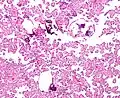

The tumor is neuroectodermal in origin and similar in structure to a normal choroid plexus. They may be created by epithelial cells of the choroid plexus. Papillary fronds lined by bland columnar epithelium are visible under the microscope. Normal absences include mitotic activity, nuclear pleomorphism, and necrosis.[10] Tumors have positive immunohistochemistry for cytokeratin, vimentin, podoplanin, and S-100.[11] Up to 20% of choroid plexus papilloma patients may test positive for glial fibrillary acidic protein (GFAP).[12] Studies have found that fourth ventricle cancers express more S100 than lateral ventricle tumors, and older patients (over 20 years) express more GFAP and transthyretin than younger patients.[13] Some individuals with choroid plexus papilloma have germline TP53 gene mutations, according to genetic analyses.[14] These cancers rarely exhibit nuclear p53 protein positivity. Aicardi syndrome, hypomelanosis of Ito, and 9p duplication are syndromic correlations of choroid plexus papilloma.

Micrograph of a choroid plexus papilloma. H&E stain. -